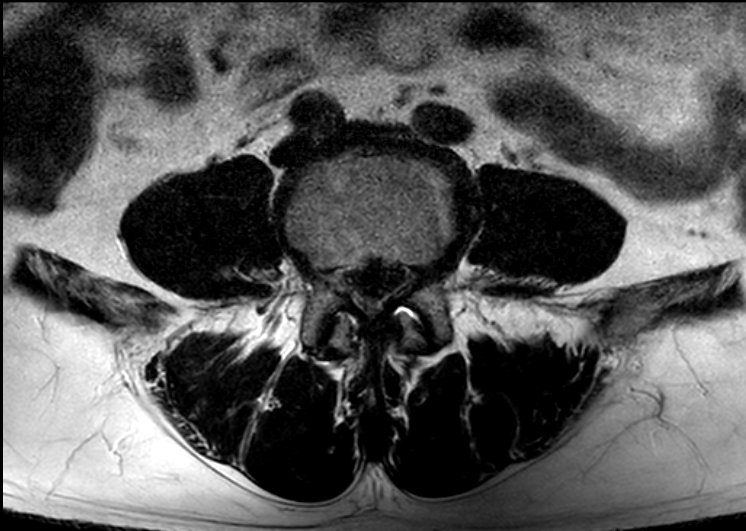

| Subject | 척추협착증 관련 질문 드립니다. |

https://www.redtea.kr/pb/pb.php?id=qna&no=7662 엊그제 글을 한 번 올렸는데 다시 올리는 이유는 MRI 사진을 환자인 가족에게 파일로 받았기 때문에 더 정확한 설명을 들은 수 있지 않을까라서 입니다. 다른 병원에서 진료만 받아보려고 토요일에 가서 파일을 받았다네요. 이미 한 번 질문을 드렸고 많은 조언을 받았기 때문에 다시 올리는 게 겸연쩍기도 하고 한 달 간 다른 병원 몇 군데를 가볼 예정이지만 그래도 하나라도 많은 조언을 듣고 싶어서요. 진단을 해주신 대학병원 의사선생님을 못 믿는 건 아닌데 앞서 글에서도 설명드렸듯이 한 달 간 휴직을 하는 것에 대해서나 당뇨나 다른 병들 때문에 수술보다 다른 시술이나 치료가 좋지 않을까 싶어서 입니다. 물론, 여러 의사선생님들이 수술하라고 하시면 예정대로 빠르게 수술할 생각이고요. 사진은 측면 4장 단면(?) 3장 정도 있는데 잘 몰라서 우선 2장만 올려봤습니다. 같은 내용으로 번거롭게 두번이나 글 올려서 홍차넷 여러분께 죄송합니다. 0